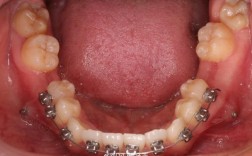

正畸调整个别牙转矩簧

正畸治疗中,牙齿的精准移动是核心目标之一,而转矩控制作为三维方向调整的关键,直接影响治疗结果的稳定性和美观性,在众多转矩控制装置中,个别牙转矩簧因针对性强、操作灵活,成为解决单颗牙齿转矩异常的常用工具,本文将从转矩簧的原理、类型、临床应用及...